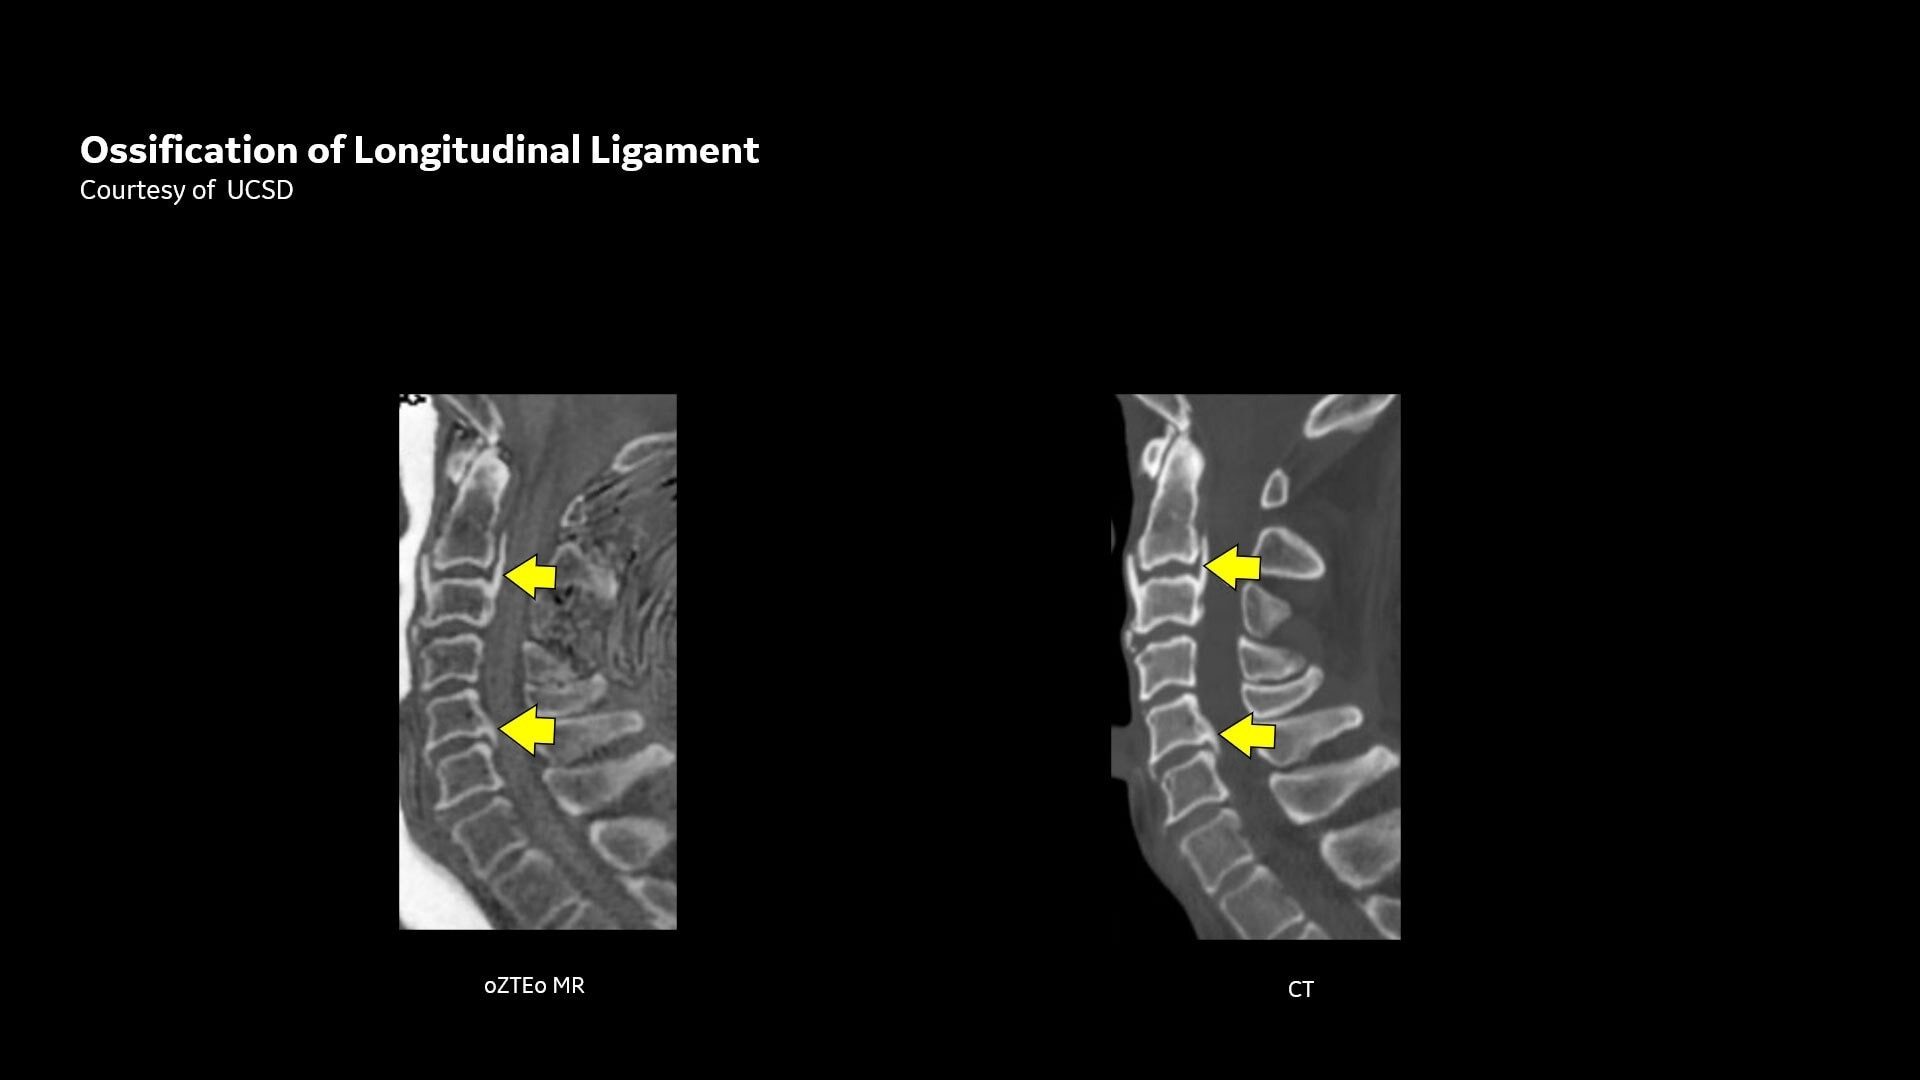

One-stop Orthopedic Shop

Provides cortical bone information co-registered with the soft tissue series

CT-like Image Contrast

Without ionizing radiation, offers an alternative for pediatric and pregnant patients